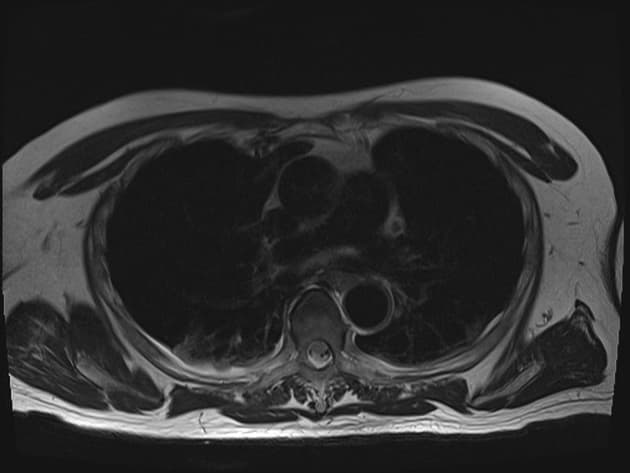

Coronal MRCP

Long cystic duct remnant with choledocholithiasis after cholecystectomy

Các đợt sốt và đau bụng cấp tính tái diễn. Tiền sử phẫu thuật cắt túi mật sáu năm trước do viêm túi mật cấp tính.

MRCP cho thấy mỏm ống túi mật dài chạy song song với ống gan chung và hợp lưu ngay phía trên đầu tụy. Nhiều hình khuyết trong lòng tại vị trí nối với mỏm ống túi mật và dọc theo đoạn xa ống mật chủ. Giãn nhẹ đường mật trong gan phía thượng lưu, rõ rệt hơn ở thùy gan trái. Thảo luận: Mỏm ống túi mật dài là một biến thể giải phẫu sau phẫu thuật đã được ghi nhận sau phẫu thuật cắt túi mật và có thể tạo điều kiện thuận lợi cho việc hình thành sỏi mật tái phát và viêm đường mật. Chiều dài mỏm lớn hơn 1 cm được coi là có ý nghĩa lâm sàng, đặc biệt khi kết hợp với vị trí cắm thấp của ống túi mật và đường đi song song với ống gan chung, như có thể thấy trên MRCP. Cấu trúc như vậy có thể đóng vai trò là ổ đọng gây ứ mật và hình thành sỏi, đồng thời có thể giả dạng sỏi sót hoặc các biến chứng đường mật sau mổ khác. Do đó, việc nhận diện chính xác là rất quan trọng để tránh diễn giải sai và chẩn đoán chậm trễ. MRCP cung cấp một đánh giá không xâm lấn và có độ chính xác cao về giải phẫu đường mật sau phẫu thuật, cho phép mô tả rõ ràng mỏm ống túi mật, vị trí cắm và các hình khuyết trong lòng đi kèm. Ở những bệnh nhân có các triệu chứng đường mật tái phát sau phẫu thuật cắt túi mật, MRCP là phương pháp chẩn đoán hình ảnh được lựa chọn hàng đầu để hướng dẫn xử trí phù hợp, bao gồm can thiệp nội soi hoặc phẫu thuật.

Mỏm ống túi mật dài kèm sỏi ống mật chủ sau phẫu thuật cắt túi mật